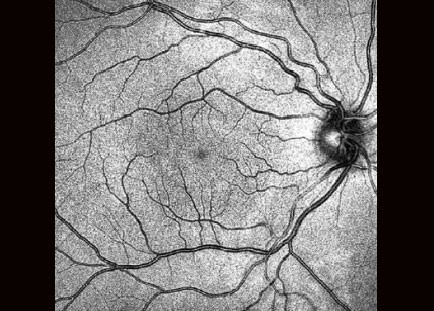

Вбудований скануючий лазерний офтальмоскоп значно сприяє якості сканування та простоті використання. Забезпечення відстеження сітківки у режимі реального часу дозволяє точно контролювати обстеження..

Скануючий лазерний офтальмоскоп точно слідкує за обстеженням та автоматично підлаштовує позицію сканування під те саме положення, що було під час попереднього сканування. Для надійного порівняння програмне забезпечення автоматично обирає однакові параметри сканування.

Часом, мимовільні рухи очей під час дослідження неминучі. З вбудованим скануючим лазерним офтальмоскопом з технологією відстеження сітківки у реальному часі система дозволяє встановити ту саму позицію сканування автоматично. В результаті трекінг сітківки Xephilio OCT-значно знижує артефакти руху та таким чином забезпечується постійна висока якість зображення.